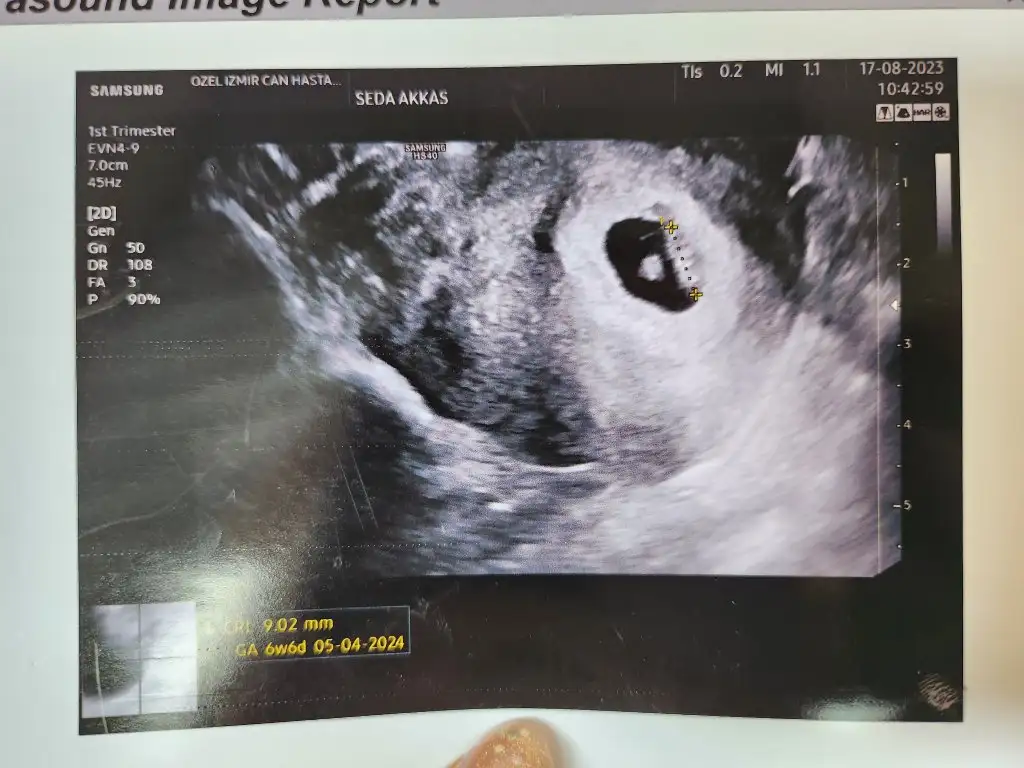

Bugün kalp atisimizi duyduk kizlar

• 20230817_111817.webp

20230817_111817.webp

46,2 KB · Görüntüleme: 55